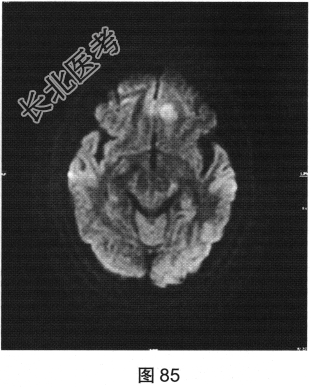

- 多项选择题2.[提示]患者行MRI检查,如图80~图85所示。患者MRI检查的阳性影像学表现包括( )

A、MRI示右侧大片水肿

B、病变增强扫描未见明显强化

C、MRI示左侧大片水肿

D、FLAIR呈稍高信号

E、病变增强扫描可见明显强化

F、FLAIR呈稍低信号

G、MRI示左侧异常信号影

H、MRI示右侧异常信号影